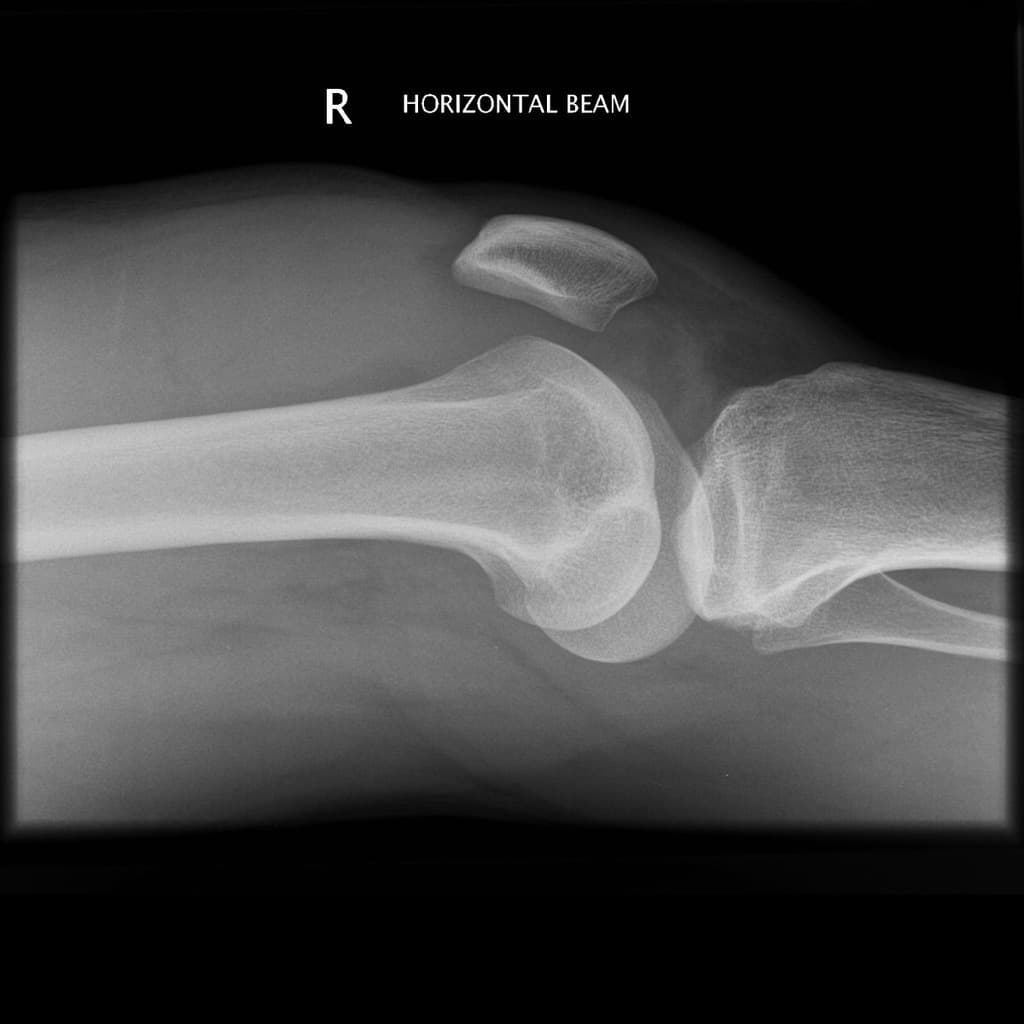

Lipohaemarthosis (dịch mỡ - máu trong khớp)

- "Lipohaemarthrosis là dấu hiệu đặc hiệu của gãy xương dạng khớp, thường do gãy plateau chày, khi mô tủy chứa mỡ tràn vào khoang khớp."

- "Sự xuất hiện của mức dịch - mỡ trên X-quang gối nghiêng ở bệnh nhân chấn thương gợi ý lipohaemarthrosis và cần đánh giá thêm bằng CT hoặc MRI."

Lipohaemarthrosis là tình trạng có cả mỡ và máu trong khoang khớp, thường gặp nhất ở khớp gối sau chấn thương. Nó xảy ra khi một gãy xương dạng khớp làm vỡ khoang tủy xương, cho phép mỡ tủy tràn vào khoang hoạt dịch, tạo nên mức dịch - mỡ đặc trưng trên X-quang nghiêng khi bệnh nhân nằm nghiêng hoặc tia ngang. Nguyên nhân phổ biến nhất là gãy plateau chày, mặc dù các gãy xương dạng khớp khác như gãy đầu dưới xương đùi hay xương bánh chè cũng có thể gây ra hiện tượng này. Việc phát hiện lipohaemarthrosis rất quan trọng vì nó gợi ý một gãy xương ẩn không nhìn thấy rõ trên X-quang ban đầu. Cần chụp CT hoặc MRI để đánh giá đầy đủ kiểu gãy và tổn thương mô mềm. Điều trị phụ thuộc vào mức độ di lệch, tính ổn định và tổn thương đi kèm, từ bất động đến cố định phẫu thuật.